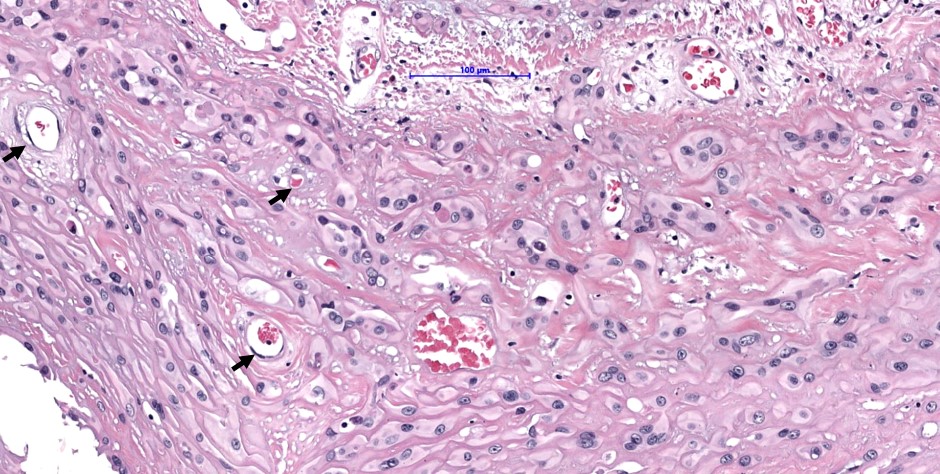

- Some tumor cells have intracytoplasmic, round, clear vacuoles representing small vascular lumina, which may contain erythrocytes

- Up to 10% of cases exhibit frank malignant features of prominent nuclear pleomorphism, increased mitotic activity, solid growth or necrosis; these tumors resemble epithelioid angiosarcoma and have a more aggressive behavior (Am J Surg Pathol 2008;32:924)

Microscopic (histologic) images